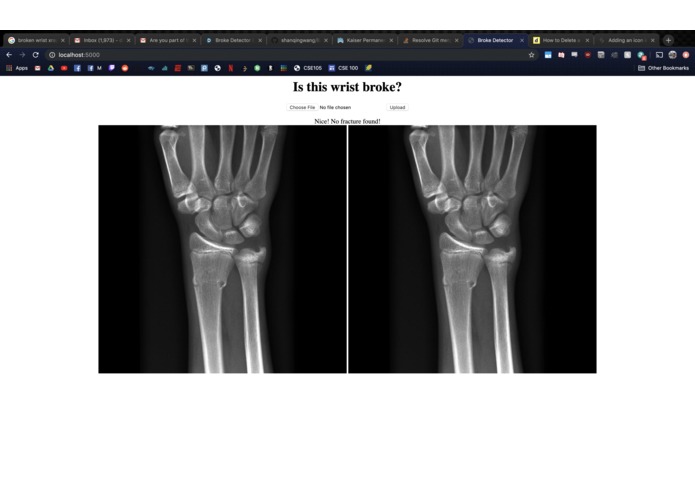

Broke Detector is a simple tool to help analyze the site of wrist injury. It helps doctors decide a) whether the bones are broken or not (which is admittedly very simple for humans, but not for computers) and b) provides tools such as a protractor to provide an objective measurement of how misaligned bones are. Broke Detector aims not to replace the orthopedist, but to aid them.

The actual detection algorithm is the guts of this project (no machine learning involved). The process is as follows: Thresholding: Reasons for this will be listed in the next section, we did this using color histograms to determine the percentile of certain pixel values. Edge detection: We used a simple Söbel kernel (however, not the default opencv one) to handle edge detection, as it was simple to detect only horizontal edges. Hough transform: This is the guts of the algorithm, which decides where horizontal lines are in the X-Ray. It sounds dumb, but choosing the lowest isolated horizontal line almost always results in finding the break in the bone. Flask: We developed a locally hosted web application which supports uploading from the computer. The HTML formatted site displays the results of the Python calculations.

ML isn't the end-all and be-all for computer vision. Don't use a slow Python GUI framework, just make a web-app instead. Opencv is fun.